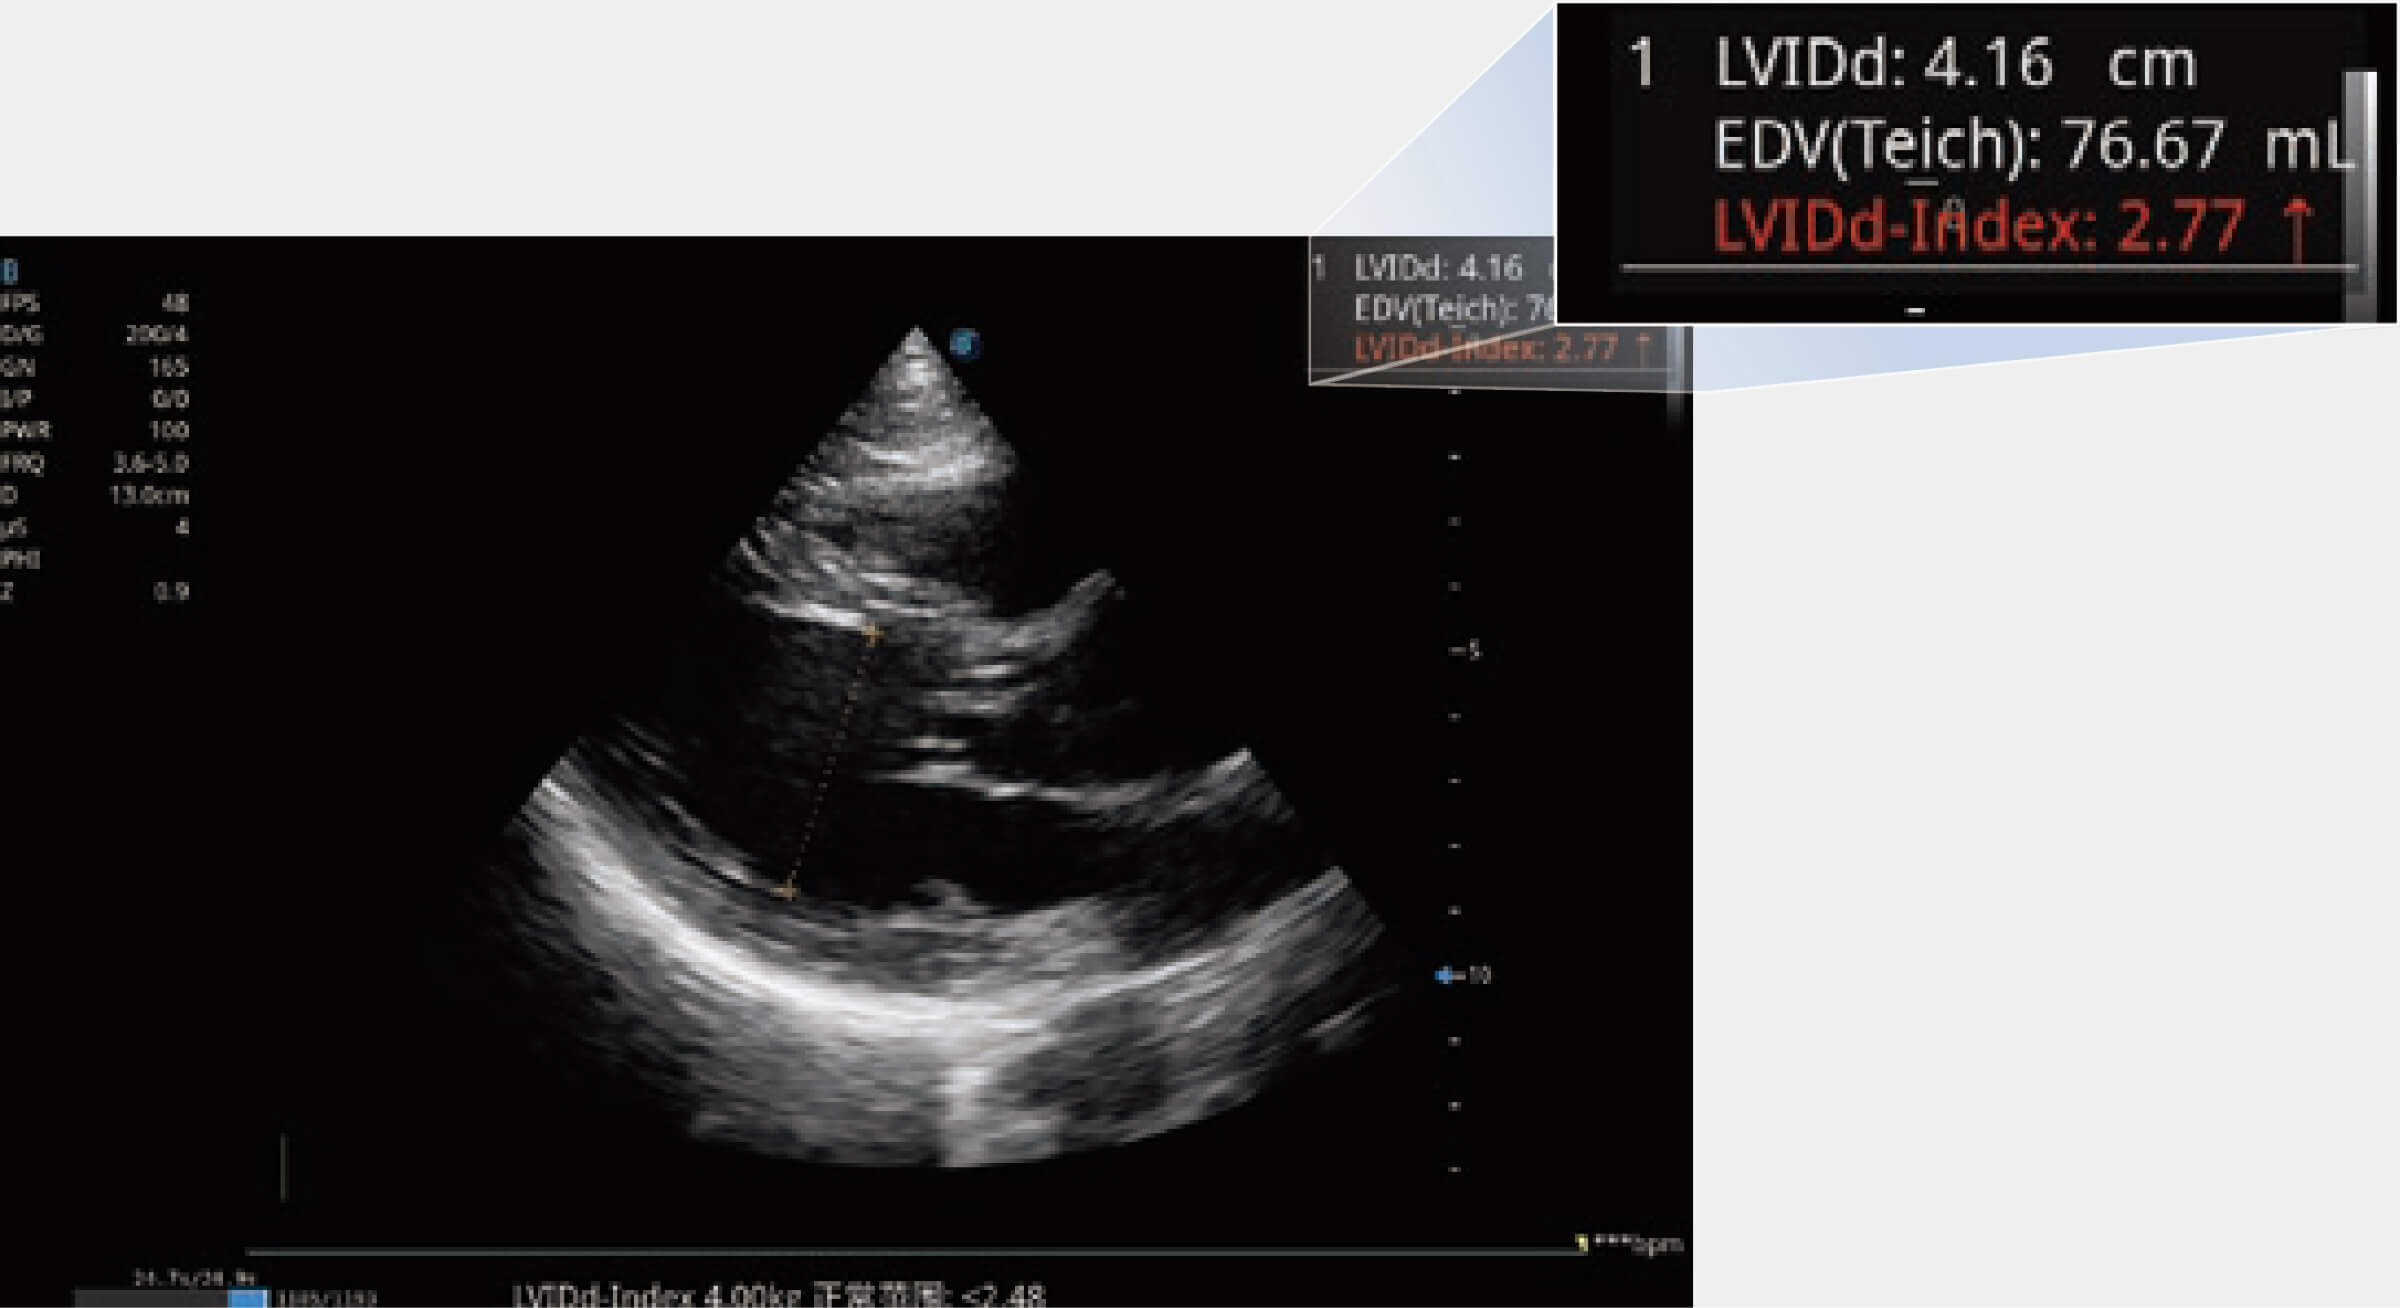

當(dāng)心臟測(cè)量結(jié)果超出正常范圍時(shí),可實(shí)時(shí)預(yù)警提示動(dòng)物醫(yī)生,減少疾病漏診概率。